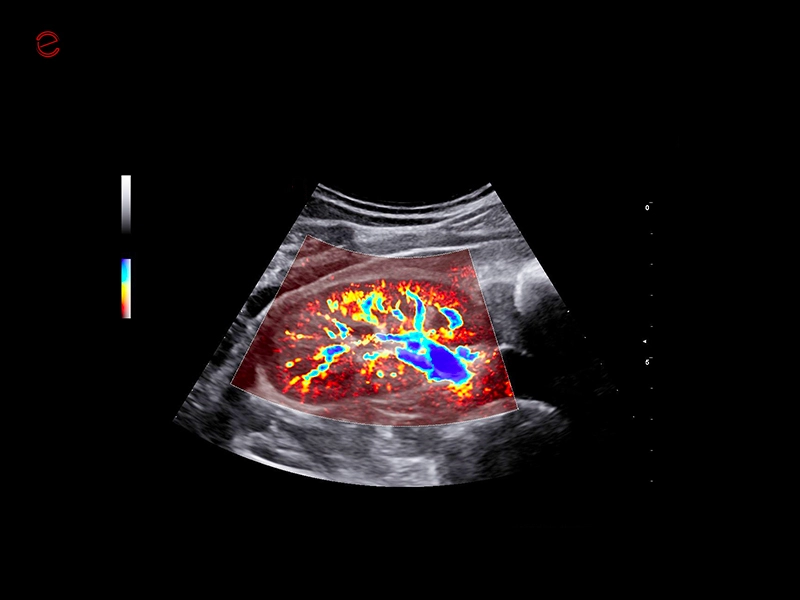

The MyLab™C30 compact ultrasound machine is specifically designed to meet the demands of everyday clinical practice for fast ultrasound access, versatility of use, and space constraints. All this has been achieved without compromising image quality and ultrasound performance. By sharing advanced imaging technologies and transducers with our high-end systems, the MyLab™C30 delivers high quality images and clinical information in a truly compact ultrasound device.

Elevated performance for enhanced diagnostic insights

Featuring the ClearWave Architecture, which combines Esaote’s advanced XBeamforming and XSmart Postprocessing technologies, the MyLab™C30 incorporates state-of-the-art imaging technologies to set a new standard for image quality, giving professionals diagnostic confidence wherever they need it. Maximize the performance of the MyLab™C30 with its wide range of probes for all clinical needs, from daily routine to the most advanced expectations. Equipped with a wide range of advanced features and an accelerated workflow powered by Artificial Intelligence, the MyLab™C30 is your portable ultrasound device that knows no boundaries.